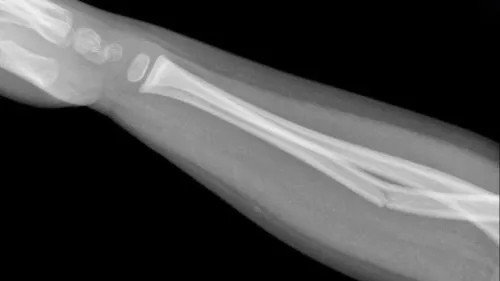

Để hiểu gãy xương cành tươi là gì, hãy hình dung việc uốn một cành cây non: thay vì gãy gập làm đôi như cành khô, nó chỉ bị nứt một bên vỏ trong khi mặt đối diện vẫn gắn kết liền mạch.

Hiện tượng gãy cành tươi (Greenstick fracture) ở trẻ em cũng tuân theo nguyên lý cơ học tương tự, xảy ra khi lực uốn ép khiến một bên vỏ xương nứt vỡ nhưng không làm đứt lìa màng xương phía bên kia.

Nhờ đặc tính dẻo dai này, khung xương của trẻ không bị gián đoạn hoàn toàn hay tạo ra các mảnh vỡ rời rạc như người lớn, giúp trục xương dù có thể cong lệch nhưng vẫn giữ được sự ổn định và không biến dạng quá nghiêm trọng.

Do lớp mỡ dưới da và màng xương dày ở trẻ thường làm lu mờ cảm giác sờ nắn lâm sàng, chụp X-quang trở thành tiêu chuẩn cốt lõi để xác minh chuẩn xác gãy xương cành tươi là gì trên phương diện giải phẫu.

Thông qua phim chụp thẳng và nghiêng, bác sĩ không chỉ nhìn rõ phần vỏ xương nứt vỡ ở mặt lồi hay uốn cong ở mặt lõm, mà còn đo lường được chính xác góc lệch; từ những dữ liệu không gian trực quan này, y bác sĩ mới có đủ cơ sở khoa học để quyết định có cần tiến hành nắn chỉnh trục xương hay không.